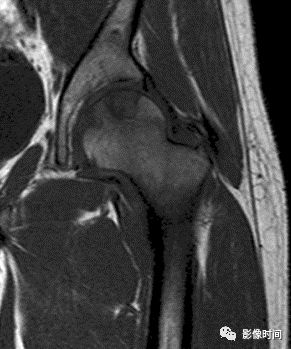

肿瘤突破关节软骨向关节腔发展时, 可表现为关节面破坏、塌陷(图 17), 关节腔内出现软组织肿块。少数良性骨肿瘤如软骨母细胞瘤, 亦可超越骺板向两侧发展或突入关节腔内, 此为肿瘤膨胀生长所致, 而非浸润性破坏。

图 17  关节软骨破坏:骨肉瘤